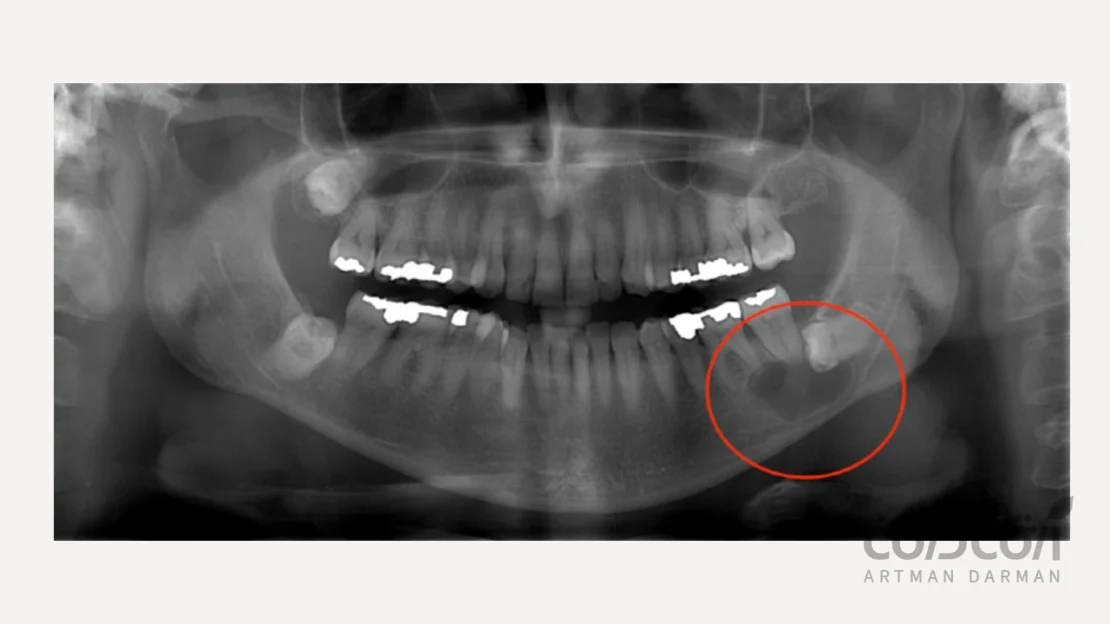

کیست های دنتی-ژروس (Dentigerous Cysts)

کیست دندان دنتیژروس که فولیکولی نیز نامیده میشوند، در اطراف تاج دندان نهفته یا نیمه نهفته ایجاد میشوند. آنها زمانی رخ می دهند که دندان در استخوان فک گیر افتاده و کیست در اطراف آن ایجاد می شود. این ضایعات معمولا در ناحیه دندان عقل یافت می شوند.

- رادیوگرافی دندانپزشکی: از اشعه ایکس می توان برای برای مشاهده کیست و ارتباط آن با ساختارهای اطراف کمک گرفت.